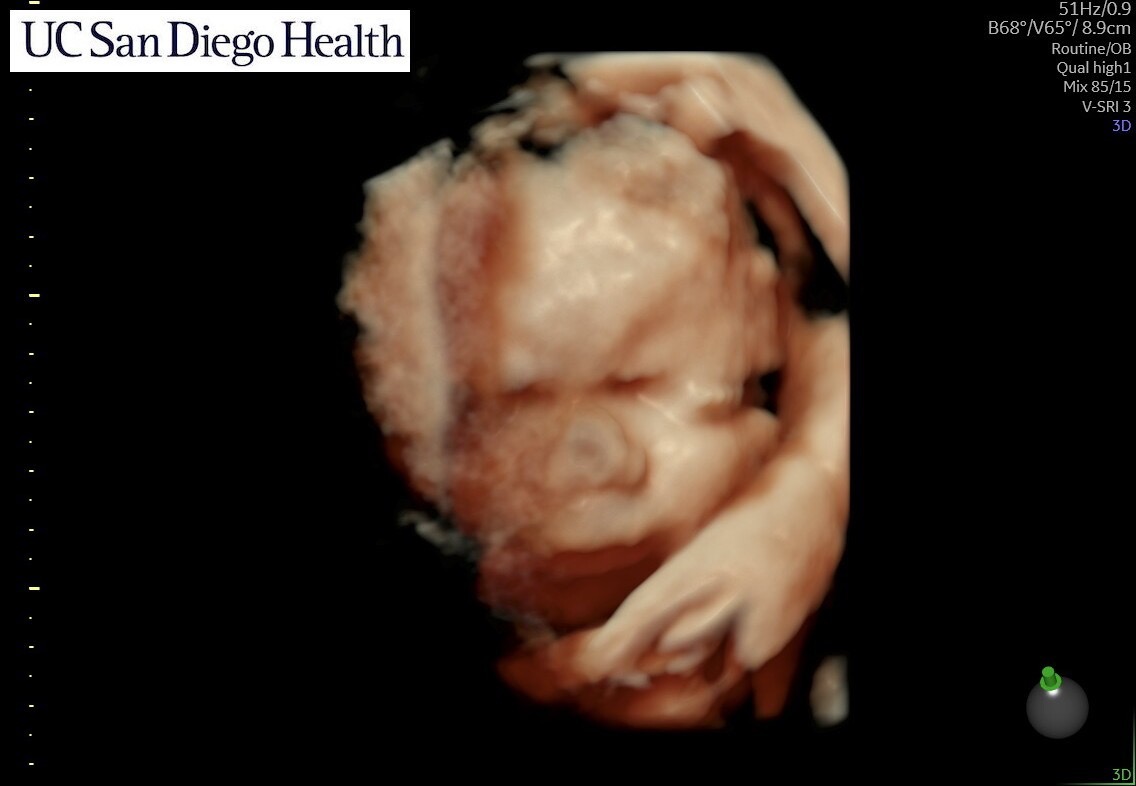

DeAngelo Has passed Away Sep 15 2025 @ 9am.

On July 25th, 2025 we got devastating news that DeAngelo has a rare condition called CDH with a broken heart im here to ask for prayers for baby DeAngelo . We had got news about a month ago that his health wasn’t so good but with faith we continued to look forward for getting him surgery. The first clinic failed the family in telling them the baby was completely healthy. If it wasn’t for the mother wanting to change clinics and hospitals for delivery they wouldn’t have did further test for the baby in which we found out at 37 weeks he was diagnosed with a syndrome called CDLS Adding the syndrome on top of the issues he has going on we don’t know what’s going to happen to him. C section is scheduled for Monday sep 15 @ 8am. Isha is already in the hospital with high blood pressure & will be delivering the baby early @ 37 weeks & you know with that she will be needing a lot of help from Andrew who will be missing work to stay by her and the baby’s side . We don’t know if he’ll survive the intubation or if he will be born still at birth . We ask from the bottom of our hearts to help with whatever you can in case baby DeAngelo has to be put to rest . God bless.